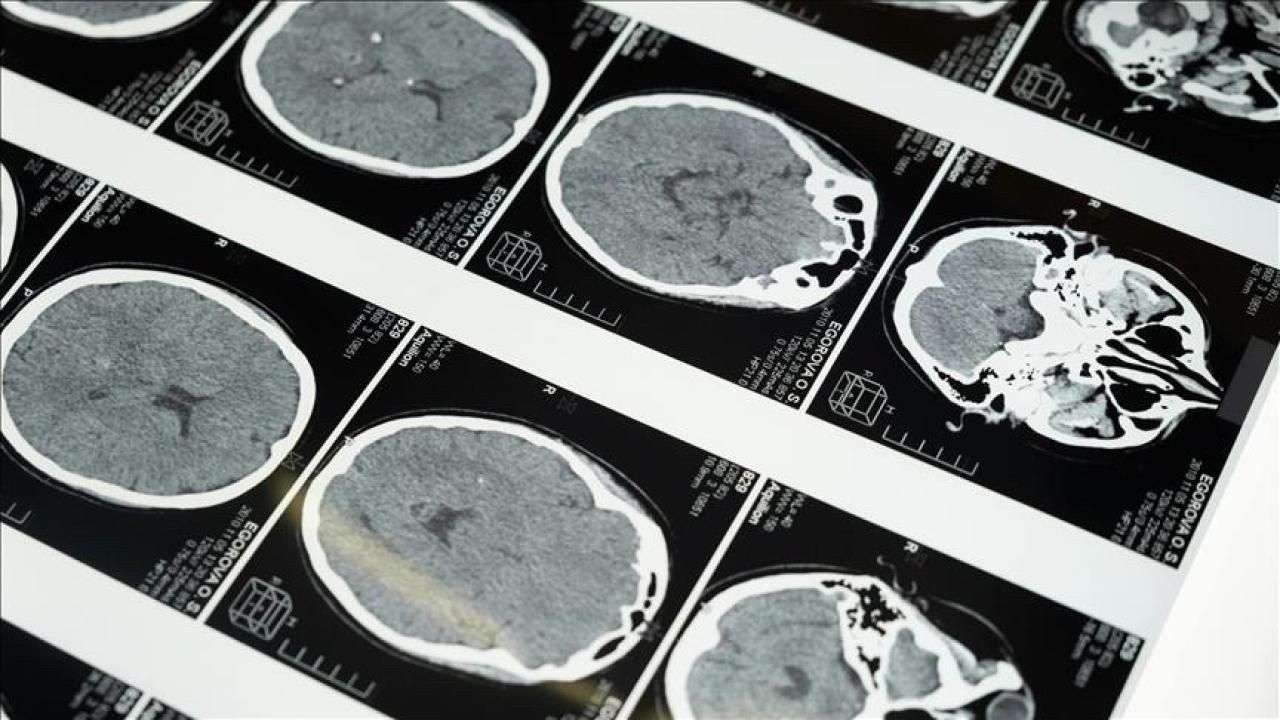

İstanbul'da düzenlenen 1. Dünya Girişimsel Nöroloji ve Nöroşirürji Kongresi'nin (WINNC 2025) düzenleme komitesinde yer alan Eskişehir Osmangazi Üniversitesi Tıp Fakültesi Nöroloji Ana Bilim Dalı Öğretim Üyesi ve İnme Merkezi Sorumlusu Prof. Dr. Atilla Özcan Özdemir, inmenin beyin damarlarının tıkanması (iskemik) ve beyin kanaması şeklinde gelişen iki türünün olduğunu söyledi.

'Özellikle pıhtıyla tıkanan beyin damarının açılmasıyla ilgili stratejiler gelişti. İnmede erken dönemde yapılan damar açma tedavileri konusunda ülke olarak iyi durumdayız. İnme tedavisinde pıhtıyla tıkalı beyin damarının anjiyo yoluyla açılması mümkün. Böylelikle hastanın 3 ay sonra, 1 yıl sonra kendi işini yapabilecek hale getirilmesi sağlanabiliyor. İnme merkezlerinde uygulanabilen bu işlemi ilk 24 saat içerisinde belirli hasta gruplarına yapabiliyoruz. İlk 24 saat çok kritik, bu müdahaleler de sadece inme merkezlerinde yapılabiliyor.'